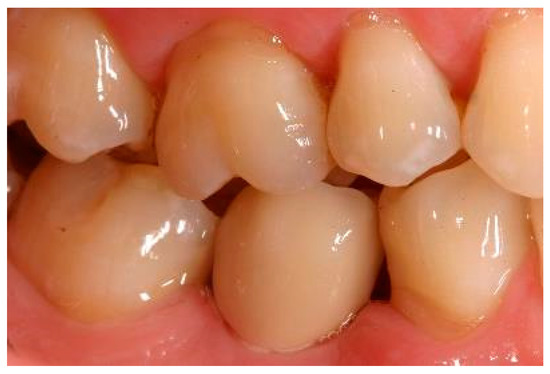

Clinical situation at the 1-year follow-up. Lateral view.

Clinical situation at the 3-year follow-up. Lateral view.

Clinical situation at the 5-year follow-up. Lateral view.